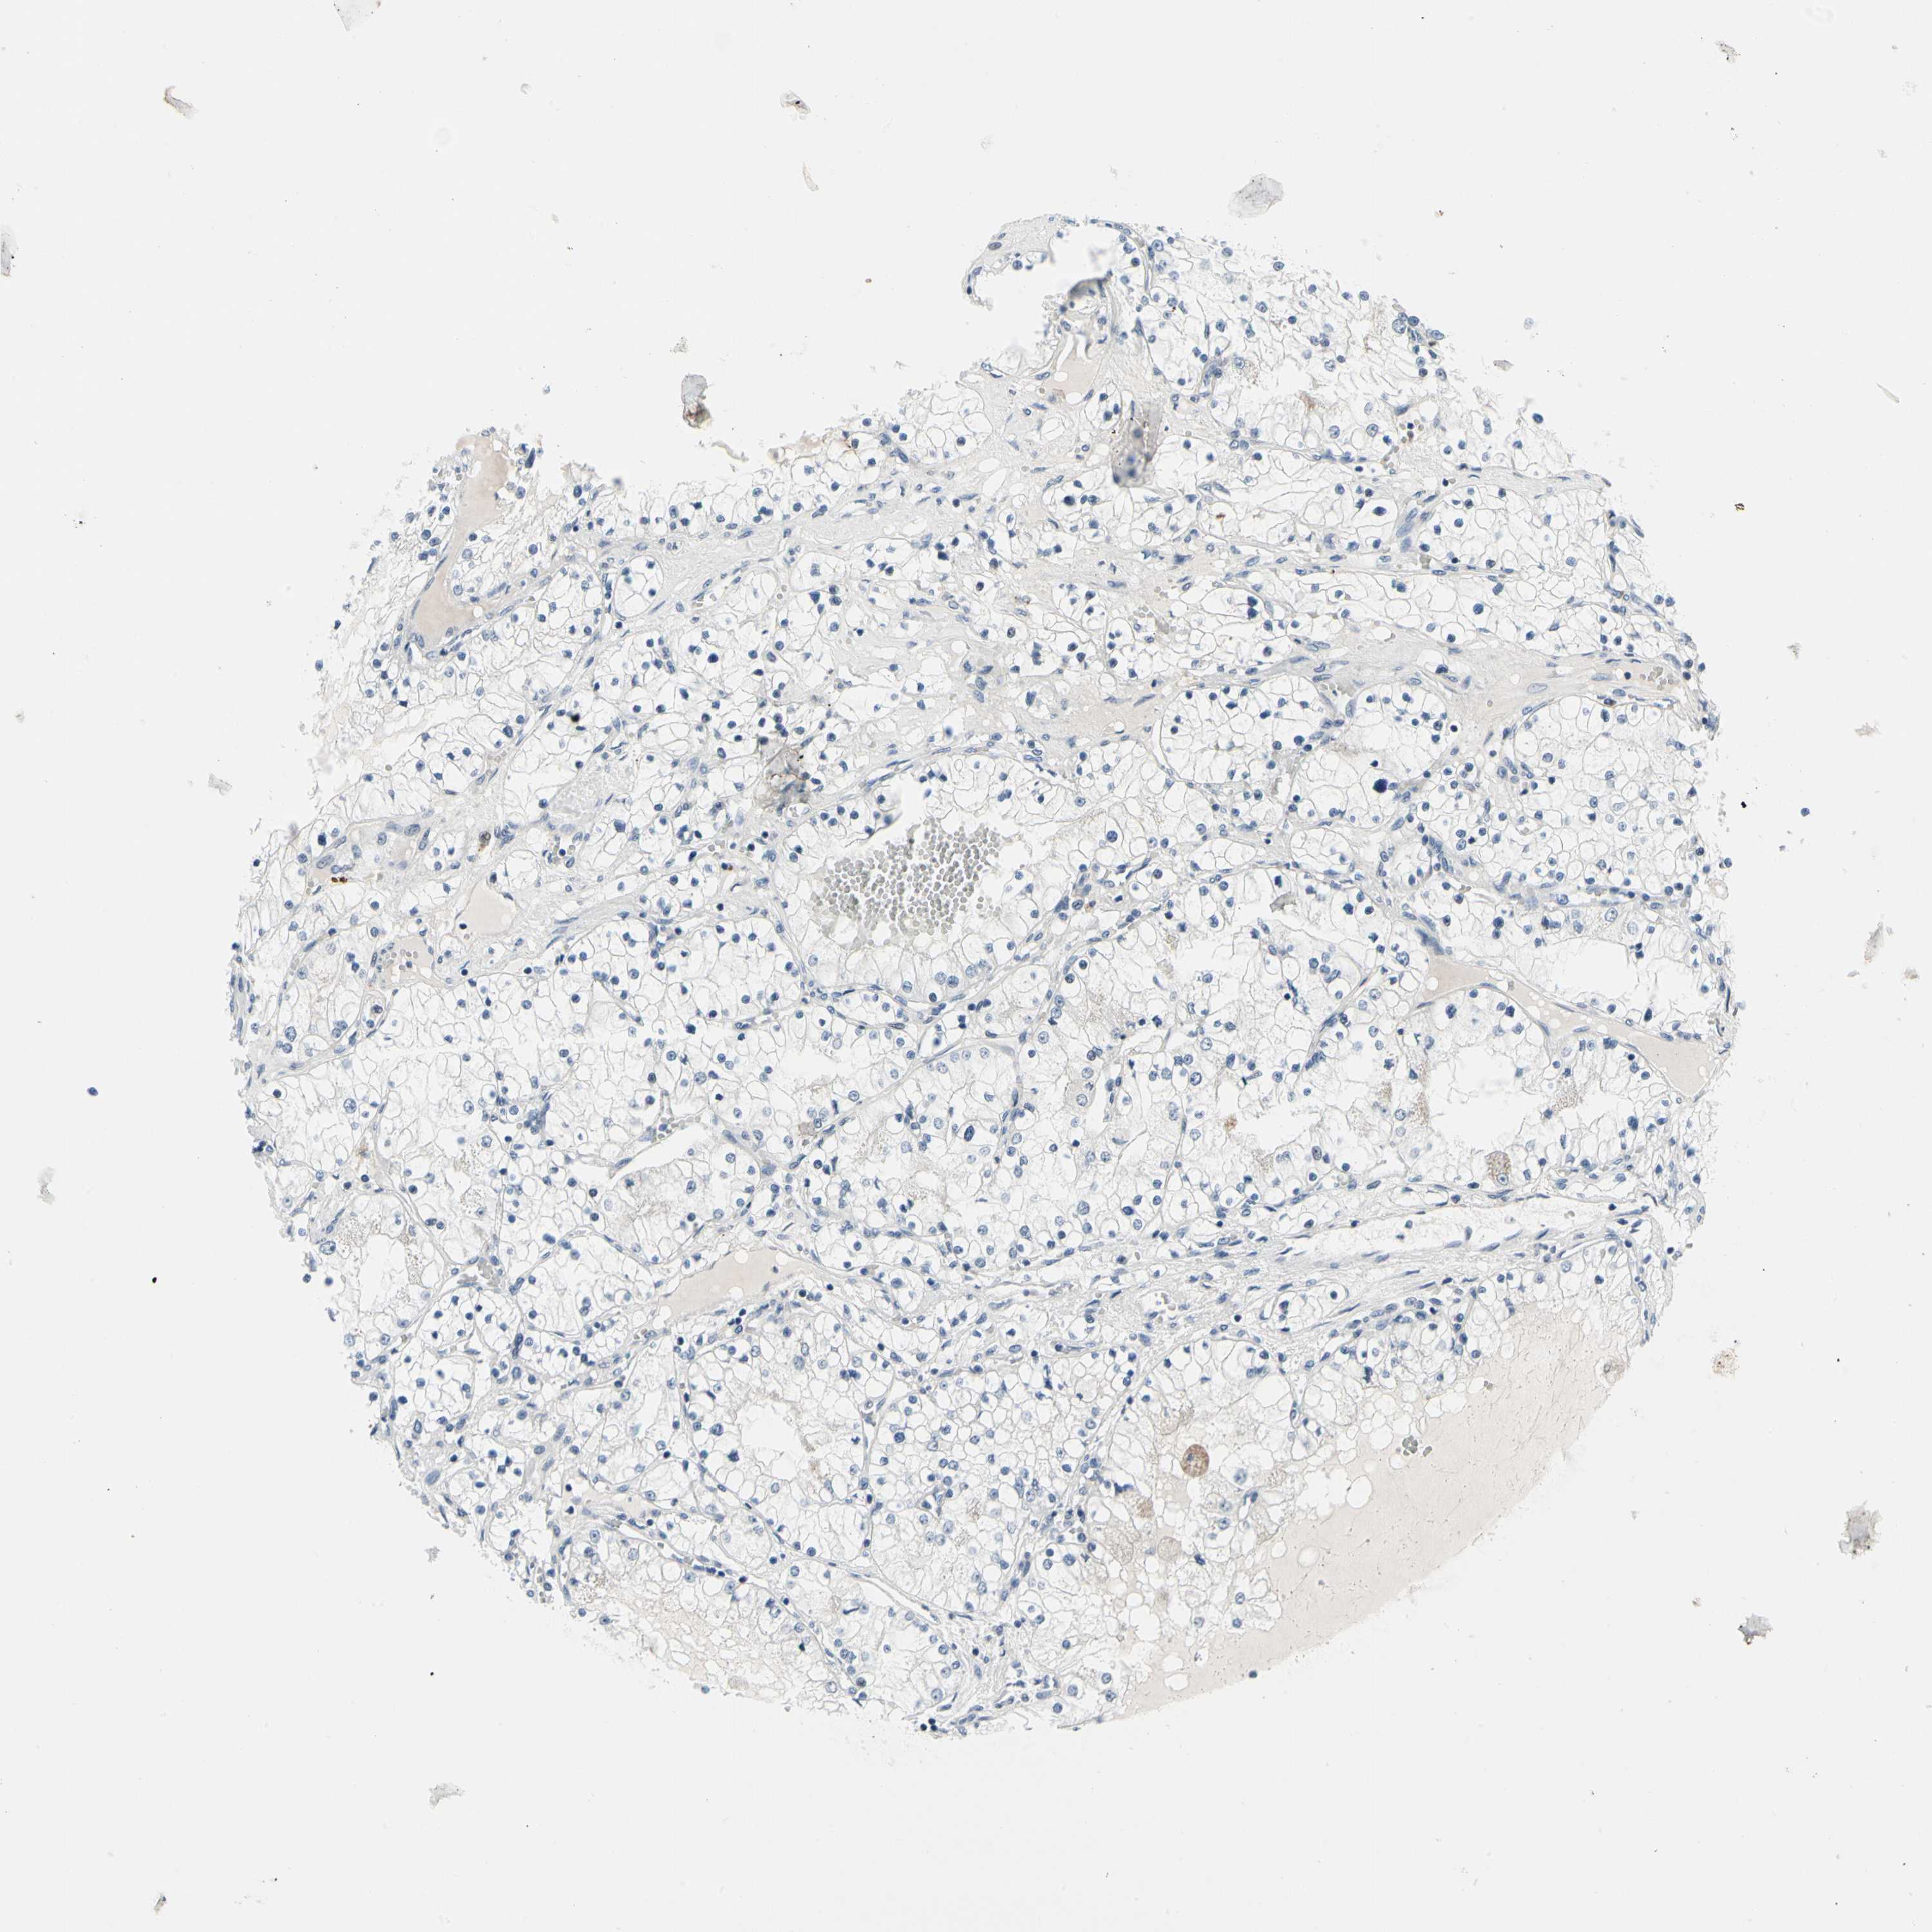

CANCER RENAL CANCER Show tissue menu

KICH TCGA KIRC TCGA KIRC VALIDATION KIRP TCGA PROTEIN RCC CPTAC PROTEIN EXPRESSION